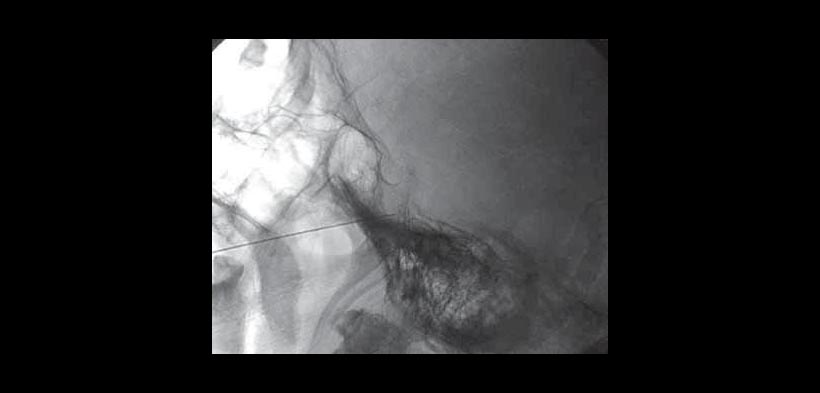

Fig. 1. Rizotomía percutánea con radiofrecuencia. Colocación del paciente en decúbito ventral con hiperextensión.

Fig. 2. Rizotomía percutánea con radiofrecuencia. Visualización del agujero oval con la utilización de un equipo de rayos en proyección anteroposterior o ligeramente caudocraneal.

Fig. 3. Rizotomía percutánea con radiofrecuencia. Se marca el punto de entrada sobre la piel que generalmente se encuentra a dos traveses de dedo de la comisura bucal. Se inyecta anestesia local y posteriormente se accede al ganglio con una aguja desechable de radiofrecuencia.

Fig. 4. Rizotomía percutánea con radiofrecuencia. La técnica clásica consiste en localizar la rama a lesionar mediante estimulación sensitiva a 50 H entre 0-1 voltio y generar posteriormente lesiones sucesivas a partir de 60° centígrados en adelante durante 60 segundos cada lesión hasta conseguir hipoestesia en la zona deseada de la cara.